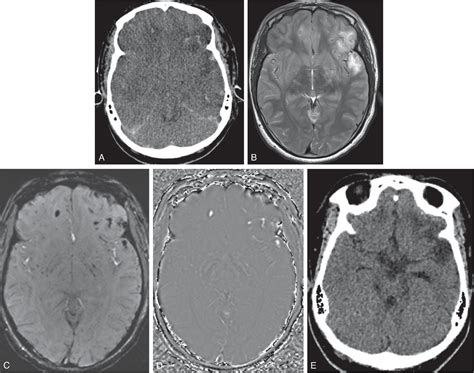

The human brain is a dynamic organ that undergoes various changes throughout a lifespan. Parenchymal volume loss, or cerebral atrophy, is essentially the loss of neurons and the connections between them. As the brain loses these cells, the physical space they occupied diminishes. This can manifest as an expansion of the sulci (the grooves on the surface of the brain) or the enlargement of the ventricles (the fluid-filled spaces inside the brain).

• Vascular Issues: Chronic hypertension, strokes, or small vessel disease can reduce blood flow to the brain, leading to cell death and subsequent tissue volume reduction.

• Traumatic Brain Injury (TBI): Significant impact or injury to the head can result in localized tissue loss as the brain heals or undergoes reactive changes.

When a radiologist identifies volume loss, they usually assess the distribution of the atrophy. Generalized atrophy refers to widespread loss across the entire brain, while focal atrophy suggests that specific areas, such as the hippocampus or the frontal lobes, are being disproportionately affected. The following table provides a snapshot of how medical professionals categorize these findings:

Asymmetric Loss Often seen in post-stroke changes or specific dementias.

The interpretation of a brain scan is rarely done in isolation. A radiologist or neurologist will compare the scan against the patient's history. For example, a 75-year-old patient with mild memory complaints and parenchymal volume loss may be viewed very differently than a 40-year-old with similar findings on an MRI. In younger patients, unexpected volume loss often triggers a deeper search for underlying causes, such as autoimmune disorders, chronic alcohol use, or nutritional deficiencies.

Technological advancements in "volumetric MRI analysis" now allow doctors to quantify brain volume more precisely than in the past. These automated programs can compare a patient's brain size to normative databases, providing a more objective measure of whether the observed loss is truly abnormal for the patient's specific age and biological sex.